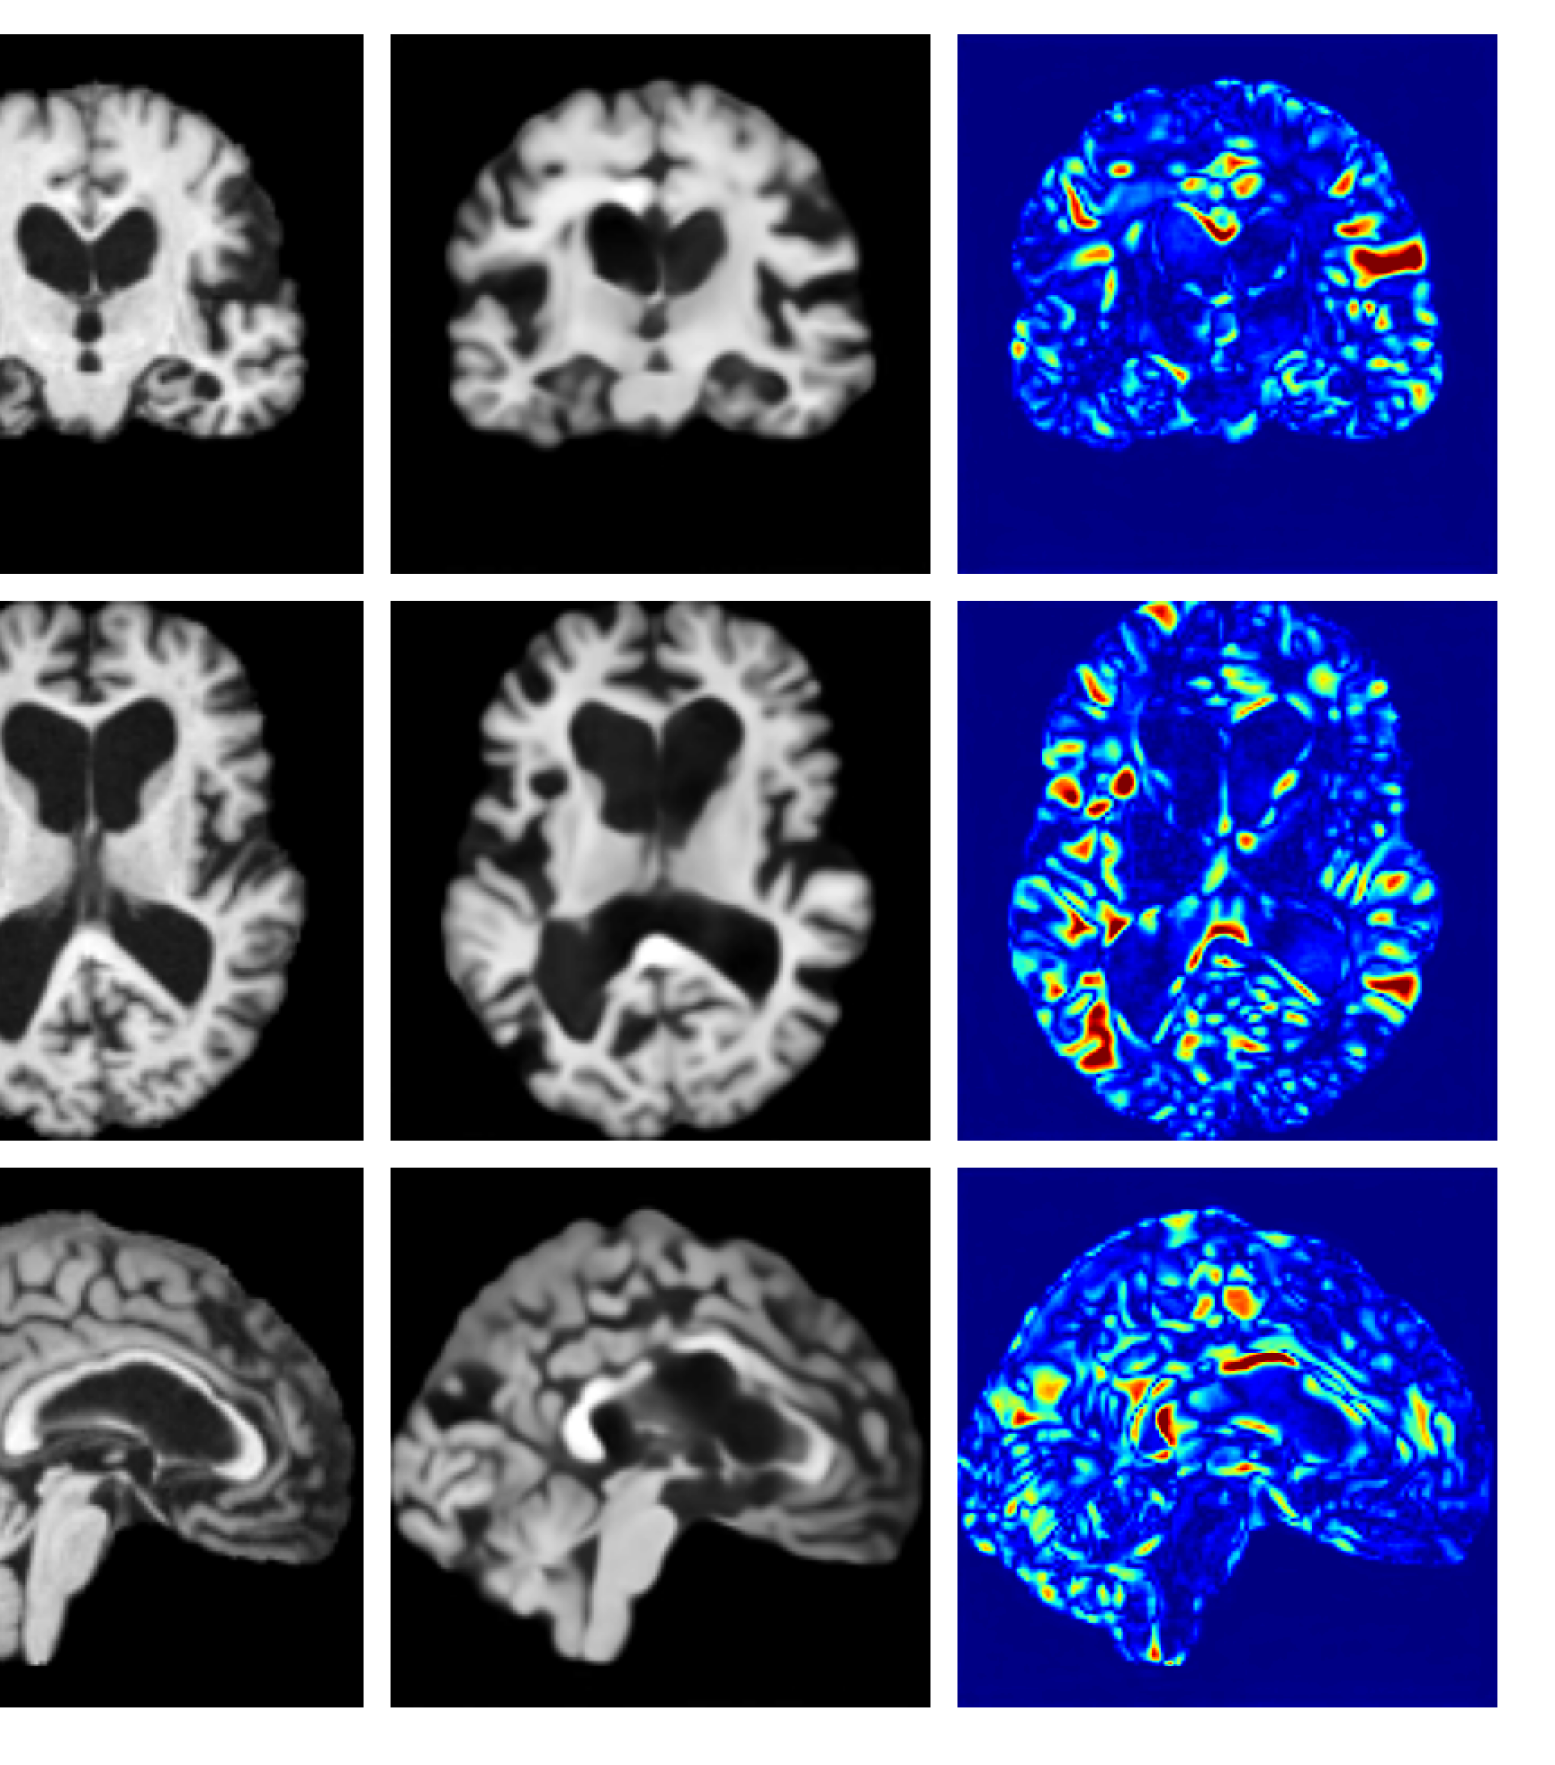

Figures 8 and 9 are enlarged versions of Figures 3 and 4 respectively, with the latter now including results from all compared methods. Figure 10 provides example reconstructions and anomaly maps for an AD subject from the ADNI disease cohort.

Figure 10: Example reconstructions and anomaly maps for an AD sample from the disease cohort of the ADNI dataset. We expect to see some inpainting of atrophied tissue whilst retaining the defining characteristics of the individual sample.